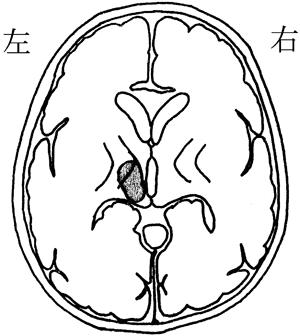

右内包後脚では、左上下肢の運動麻痺が見られるため、この選択肢は正しいです。